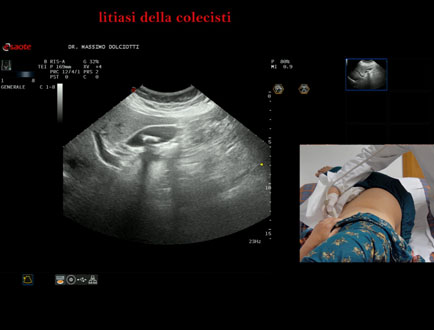

Data inserimento: 14/01/2026

Ecografia del: 12/01/2025

Strumento: Esaote MyLab Eight

Sonda: Convex Multifrequenza 1-8 MHz

Età Paziente: F 45 anni

Motivazione dell'esame: nicturia 1-2 volte.

Commento all'esame: le immagini ed il video documentano nel lume della colecisti, due immagini iperecogene, con cono d'ombra posteriore, delle dimensioni di 20,9 mm e 15,7 mm, da ricondurre a litiasi multipla.

Conclusioni: grossi calcoli della colecisti (large gallstones).